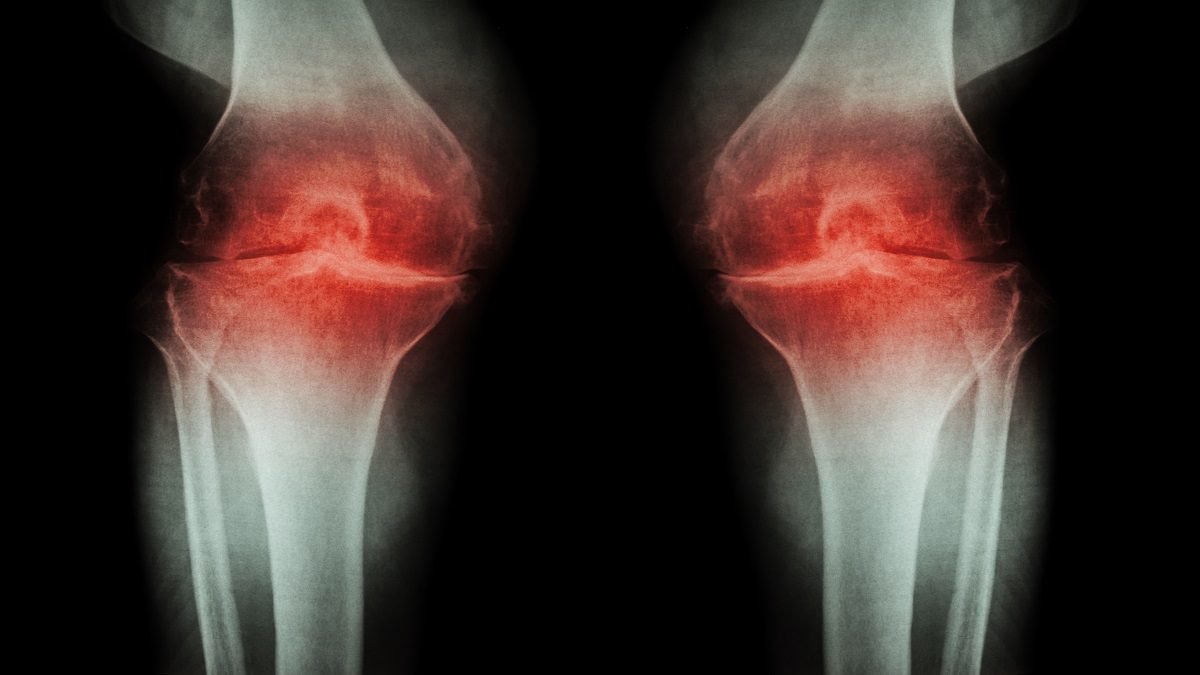

जोड़ों के लिए भी नुकसानदायक

स्ट्रेस और एंग्जायटी की वजह से शरीर के जोड़ भी कमजोर होते हैं। अत्यधिक स्ट्रेस बॉडी इंफ्लामेशन बढ़ाता है। आर्थराइटिस के मरीजों के लिए तो दिक्कत ज्यादा हो सकती है। तनाव से शारीरिक काम भी कम हो जाता है, जिससे तकलीफ बढ़ सकती है।